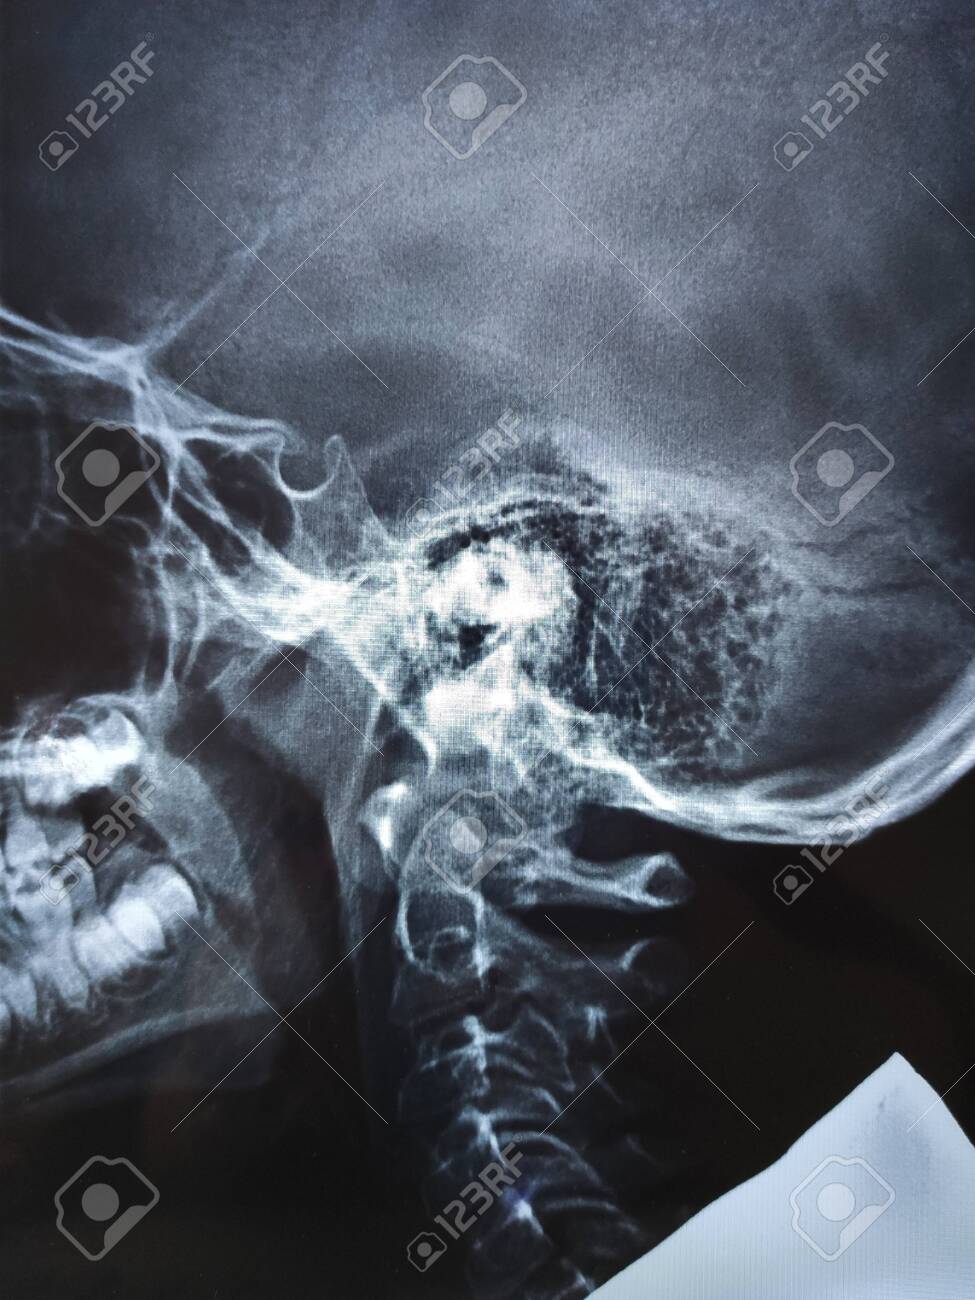

Image: Adenoides agrandados (radiografía) - Manual MSD versión para profesionales